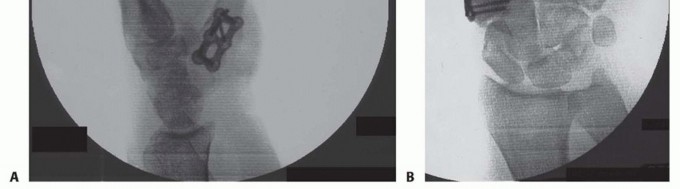

TECH FIG 3 • A. A six-hole plate is applied across the CMC joint. B. Two screws have been placed through the plate into the trapezium. C. Plate being applied onto the thumb CMC. D. Distal radius bone graft being packed into the CMC joint. Distal radius bone graft is then packed into the fusion site (TECH FIG 3D).At this time, final assessment of clinical alignment and fluoroscopic evaluation (position, bony contact, hardware placement/screw length) are performed (see FIG 2A,B).Irrigate the wound lightly with saline. Close the capsule with a nonabsorbable suture (3-0 Ethibond), repeat irrigation, and deflate the tourniquet to confirm hemostasis as the radial artery and venae comitantes are within the operative field. Close the skin with 4-0 nylon horizontal mattress sutures.If mild thumb MCP joint hyperextension is noted at this juncture, pin the MCP joint in 20 degrees of flexion with a single 0.045 Kirschner wire or consider a volar capsulodesis. In our experience, correction of the fixed flexion and adduction of the thumb metacarpal often improves MCP position with pinch so that operative intervention at the MCP joint is infrequent.Apply soft sterile dressings and a well-padded short-arm thumb spica splint.